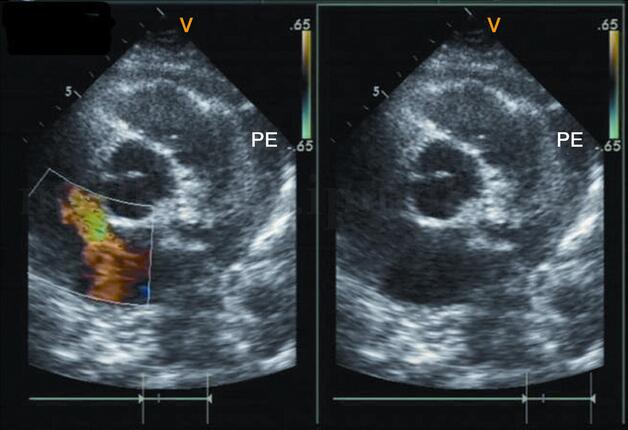

图2‐1‐220 中‐大量心包积液

A﹒左室长轴切面;B﹒心尖四腔心切面;PE:心包积液